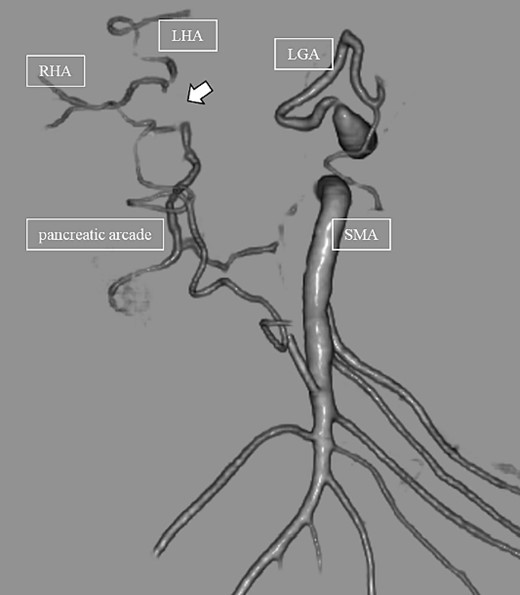

Subsequently, interventional radiology (IVR) was performed. However, because the inferior pancreaticoduodenal artery (IPDA) was very narrow, the microcatheter could not be followed, and hemostasis with IVR was difficult. Therefore, on POD 48, relaparotomy pseudoaneurysm repair was performed. The abdomen was opened through an inverted L-shaped incision, and adhesiolysis was performed, after which a pseudoaneurysm was revealed at the junction of the GDA and PHA. Four transfixing sutures with 3–0 prolene were used. After confirming that the liver blood flow was maintained, surgery was completed. However, bloody drainage from the drain was observed on POD 56. CeCT revealed a pseudoaneurysm (Fig. 3A and B). IVR was considered difficult because of the narrow blood vessels; therefore, the patient underwent a second laparotomy for hemostasis. A pseudoaneurysm was further observed at the junction between the GDA and PHA. In this operation, we used deeper and wider penetrating sutures than in the previous surgery to completely halt blood flow in the GDA. We confirmed that the blood flow to the liver was maintained; however, it was deemed weak. The patient had an uneventful postoperative course without bleeding, and CeCT performed on POD 61 confirmed the disappearance of the pseudoaneurysm. Although the blood flow in the PHA could not be confirmed, the right and left hepatic arteries were preserved (Fig. 4). On POD 76, CT revealed no liver abscesses or infarctions. The drain was removed on POD 78, and the patient was finally discharged on POD 107 without rebleeding or liver failure.

(A, B) CT on postoperative Day 56. Contrast-enhanced CT shows a pseudoaneurysm at junction of the GDA and PHA (arrow).